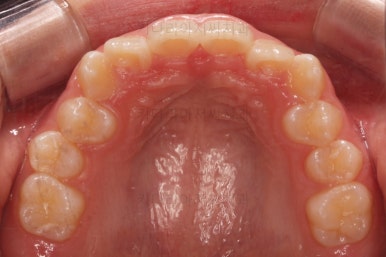

초진 시 입안의 모습입니다.

전반적으로 치열이 삐뚤삐뚤하고요.

우선 윗니에만 교정장치를 부착했습니다.

성장치료라더니 교정치료? 하실 수 있지만 윗니를 가지런하게 해준 이유는 아래턱을 앞으로 성장시켜줄려니 윗니 앞니가 옥니처럼 가로막고 있어서 아래턱이 앞으로 나올래야 나올 수 없는 상황이었어요.

그래서 앞니의 각도를 먼저 개선해주기로 했죠.

앞니의 각도가 앞으로 살아난 것이 보이실 거에요.

자연스럽게 과개교합 경향도 개선되어 어금니로 물었을 때 아래 앞니가 점점 보이기 시작하네요.